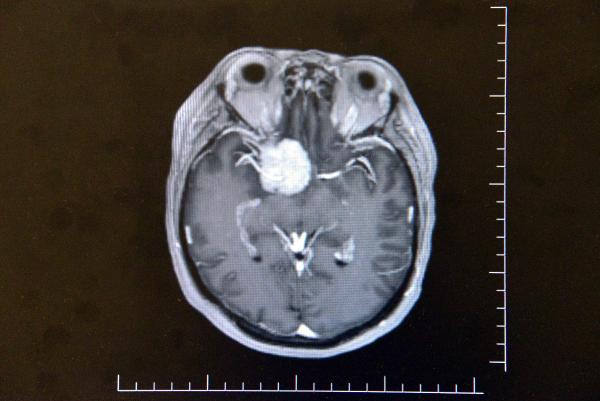

Altun tarafından yapılan muayene ve tetkiklerde Gül'ün beyninde ceviz büyüklüğünde tümör olduğu ve gözündeki sorunun tümörden kaynaklandığı tespit edildi. Altun, Ayşe Gül'e acilen ameliyat olması gerektiğini ancak tümörün ana şah damarlarının olduğu bölgede olmasından dolayı ölüm riskinin yüzde 80, yaşaması halinde ise felç kalma ihtimalinin de çok yüksek olduğunu söyledi. Tüm riskleri kabul eden Gül, Altun tarafından ameliyata alındı. Ameliyatı beyni açmak yerine endoskopik yöntemle gerçekleştiren Altun, tümörü Gül'ün burnundan çıkardı.

"Hastamız görme şikayetiyle ilgili birçok yere gitmiş ancak hastalıkla ilgili bir teşhis konulamamış. En son çekilen filminde ana şah damarlarını tamamen saran, görme sinirini tamamen kapatan, solunumla hayat merkezinin önünde geniş bir kitle olması üzerine hasta tarafıma geldi. Hastayı değerlendirdikten sonra endoskopik yöntemle kamera eşliğinde burundan girerek ceviz büyüklüğünde, 3,5 santim genişliğindeki kitleyi almaya karar verdik. Hastamız tüm riskleri kabul etti. Tabi burada önemli olan ana damarlar üzerinde geçmesi, ana damarlarını sarması, görme sinirinin üzerinde olması ve solunum merkezine doğru ilerlemesi bir risk faktörüydü. Biz bununla ilgili gerekli tedbirlerimizi aldıktan sonra ameliyata girdik. Ameliyatta başarılı bir şekilde gerçekleşti, herhangi bir görme sinirinde, ana damarlara veya solunum hayat merkezine dokunmadan tümörü tamamen burundan temizledik. Hastamız gayet iyi rahat. Beynin orta yerinde taban bölgesinde dediğimiz, 3,5 santim ebadında, ceviz büyüklüğündeki tümörümüz solunum hayat merkezinin önünü kaplaması ve oraya doğru ilerlemesi,sağ ana damarlara doğru ilerleyip tamamen içerine alması ve hipofiz bezini alttan yukarı doğru sarması, bu ebada ulaşması milyonda bir oranda gözükür. Biz bu tümörü, burundan girilerek endoskopik yöntemle tamamen ana damarlara herhangi bir zarar vermeden çıkarttık.''